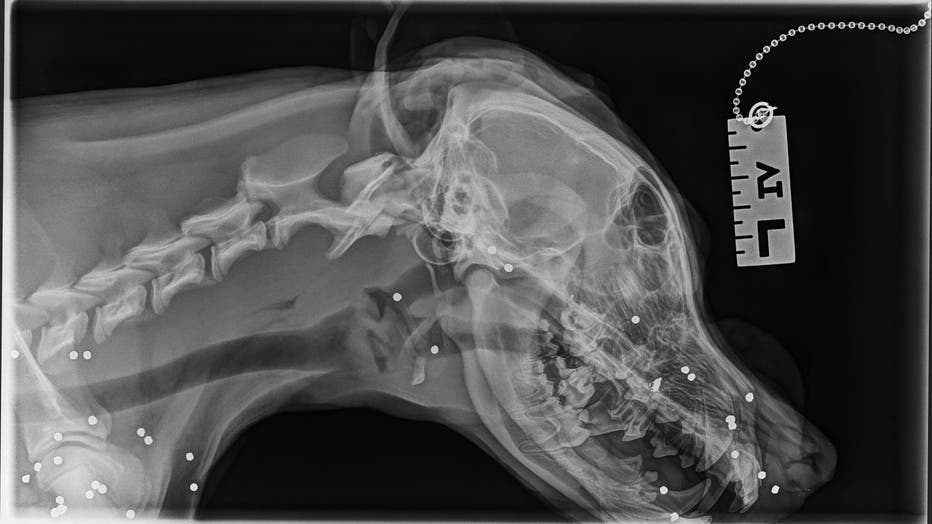

"Upon examination, SAHS veterinarians believed Tammi was hit by a car and was shot with a shotgun. Her X-rays revealed more than 70 shotgun pellets in her body," they wrote on Facebook.